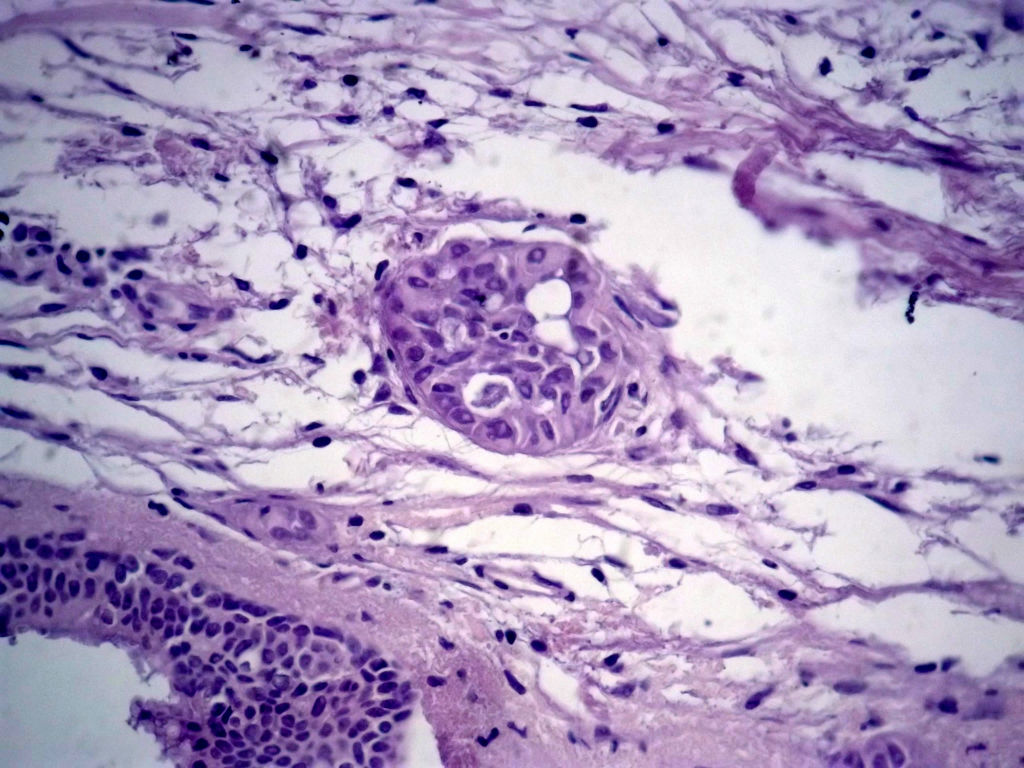

今天的一例术中冰冻。女,49岁,乳腺肿块。人气不旺,换个标题

腺病?癌?其他?(12楼常规,24楼免疫组化及会诊结果)图1

标签:浸润性导管癌 分泌癌 硬化性腺病

多谢强版主,这可是俺亲自全程操作的一张片子,俺的一点小经验是“组织要干”,“冷冻要快”,这个病例有点考验俺的神经,发上来听听高手们的意见。大体是乳腺组织一块,切面见一质硬结节,直径2cm,边界欠清,切面灰白色。强版别光夸片子漂亮啊,留下你的高见才放行

1. Most likely no invasive cancer

2 Sclerosing adenosis

3 Ductal epithelial hyperplasia

4. Bundles d Smooth muscle?

导管是乎可见双层上皮,部分上皮增生并有一定异型,考虑硬化性腺病,待石蜡。

导管可见双层上皮,部分上皮增生并有一定异型,考虑硬化性腺病

腺体与腺体之间的对比差异太大,不放心,不除外是癌,如果是我的病例,再次取材冰冻

浸润性导管癌。冰冻切片的诊断是很困难,直接诊断癌风险很大,但是在明显正常的导管间这种成片、成巢有腔的细胞团块也不是良性的表现,有的还似乎有围绕正常导管生长的倾向。诊断ADH还可以,但是不能归到任何一种DCIS的生长方式里。这例值得我好好学习。